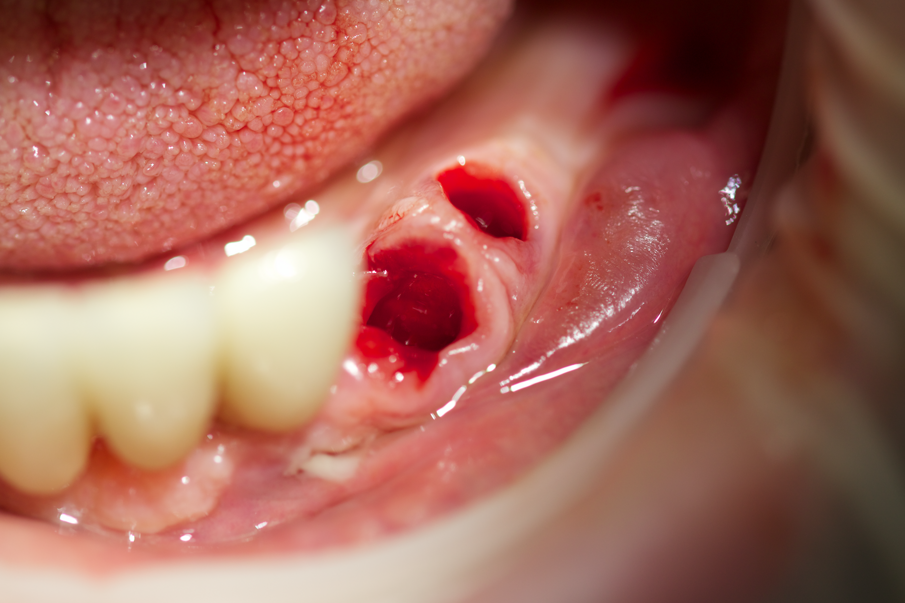

Fig.12 - Gli elementi 3.3 e 3.4 devono essere estratti.

Fig. 13 - Avulsione di 3.3 e 3.4.

Fig. 14 - Spugne emostatiche (Hemocollagene, Septodont) sono state inserite nei siti di estrazione.